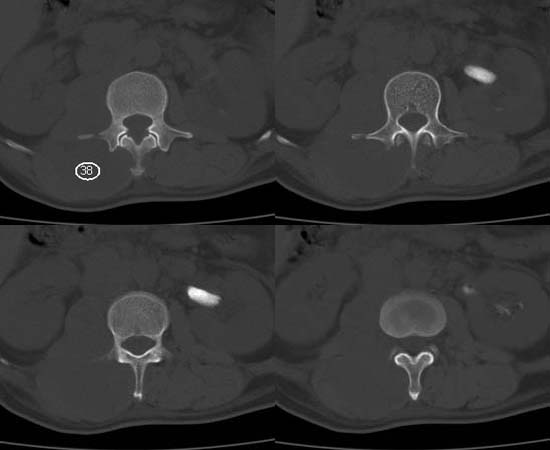

以下是引用还珠格格在2007-6-26 15:05:00的发言:[br]右侧腰大肌、同侧竖脊肌明显肿胀,呈不均匀密度减低影,右肾受压右上前移,脂肪间隙部分消失,另左侧肾盂内可见高密度影,是结石还是造影剂? 不知道病人用造影剂没有?考虑 右侧腰大肌及右侧竖脊肌寒性脓肿形成。[br][br][本贴已被 还珠格格 于 2007-6-26 15:21:35 修改过]

以下是引用小初学者在2007-6-26 15:42:00的发言:[br]1\\右侧腰大肌、同侧竖脊肌脓肿[br]2\\左侧肾盂结石

以下是引用刘明在2007-6-26 16:00:00的发言:[br][br]右侧竖直肌及腰大肌肿胀,脂肪间隙难辨,腹膜后血管旁见多个肿大淋巴结影,椎体附件右侧有压迫吸收、未见硬化迹象,考虑椎旁冷脓肿可能[br]左侧肾盂内可见高密度影,周围有毛刺,本图象是平扫,不是增强,应该是结石[br]

以下是引用hhcckk在2007-6-27 9:41:00的发言:[br]肾周筋膜增厚,胰腺影肥大,楼主是考我们了,我考虑是胰腺炎引起的腰部感染,形成的蓝棕色斑,也称gray-turner征,另外腹膜后怎么这么多的淋巴结,转移也要考虑[br]结核三个月没有骨破坏?寒性脓肿累及到竖脊肌的少见,所以我考虑结核的可能性不太大[br]左肾内高密度影,密度不太均匀,左肾有积水的表现,考虑是结石[br]期待楼主老师的结果